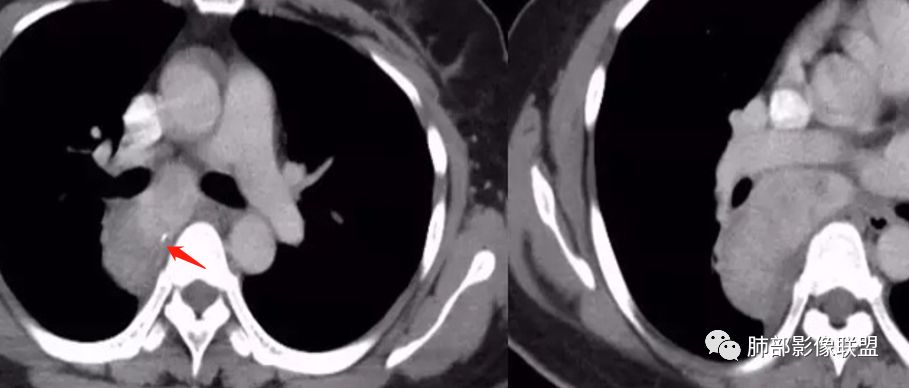

女,35岁 因“体检发现纵隔占位”入院,患者3天前体检发现肺部异常,外院胸部CT示右后纵隔占位,纵隔淋巴结影,未诉明显不适,无心慌胸闷,无头晕头痛,无恶心呕吐,无腹胀腹痛,无吞咽困难。

后纵隔占位,内见小钙化灶,增强明显强化,考虑CD。

神经源性肿瘤,内可见点状钙化,增强后强化明显,考虑神经源性肿瘤。

后纵膈,胸膜掀起,密度相对均匀,钙化,增强强化明显,接近血池密度,没有明显ab区,且椎间孔等还行,暂不考虑鞘瘤,节细胞强化有点过,神经源性放后面。后纵膈肿瘤与食管脂肪间隙存在排除食管来源。血管来源强化略偏弱一些,异位囊肿影像不符合。淋巴来源CD影像及强化符合

考虑CD可能大,神经源性待排。

后纵隔占位,不均匀强化伴分隔,病灶与7区肿大淋巴结融合,病灶与胸膜之间可见少量积液,考虑CD,鉴别神经鞘瘤。

后纵隔肿物,呈肾形,可见淋巴结门,平扫内可见钙化,显著强化,考虑CD,上下径长签别鞘瘤。

结果:巨大淋巴结增生病(Castleman,s, disease,CD)

(3)影像表现上,多发单发的圆形或类圆形软组织密度影;透明血管型在CT增强扫描时早期可显著均匀强化,与大血管强化程度相似,原因在于有较多的供养血管,及病灶的毛细血管异常增生和扩展所致;而浆细胞型强化没有前者明显